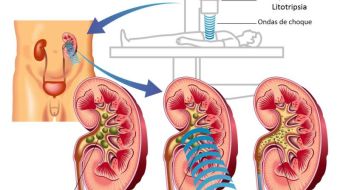

Litotripsia Extracorpórea

Uma fonte de energia emite múltiplas ondas de choque que exercem um pico de pressão num ponto focalizado no cálculo. Essa modalidade pode ter até 95% de fragmentação de cálculos menores que 1 cm, dependendo da localização, composição e anatomia renal.